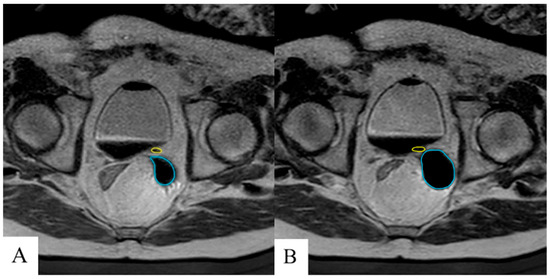

2. Methods

2.3. Ureteral Stent Placement Procedure